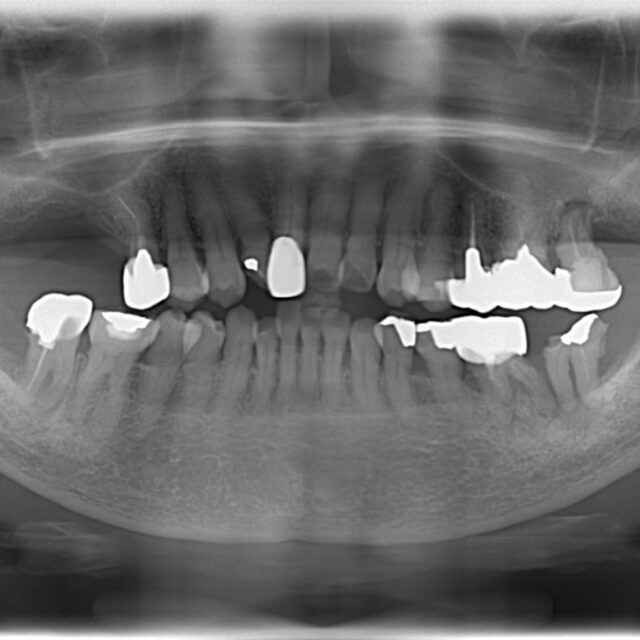

●症例投稿●インプラント治療006 〜治療方針の決定〜

- 2023年1月29日

- インプラント,咬合治療/フルマウス/咬合再構成,院内設備